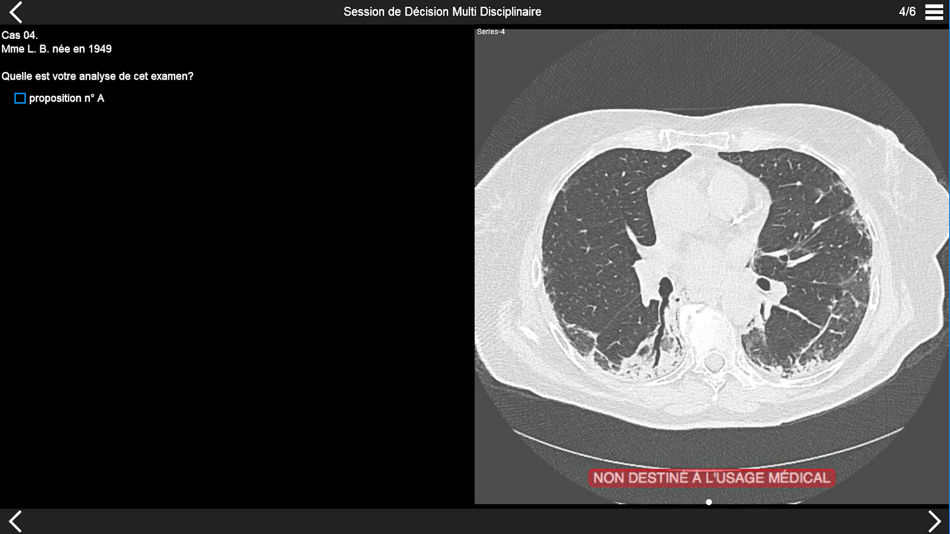

Fibrose pulmonaire 2017

Fibrose pulmonaire: Certitudes et interrogations en 2017

Organisé par Pr J. Rémy - Pr M. Rémy-Jardin - Dr JB. Faivre - Dr A. Hutt - Dr P. Felloni

Avec la participation du Pr MC. Copin - C. Chenivesse

Hôpital Calmette - CHRU de LILLE

Consultez les examens tomodensitométriques des cas cliniques de pneumopathie infiltrante présentés lors de la session de discussion multidisciplinaire qui aura lieu dans la première partie de l'après-midi.